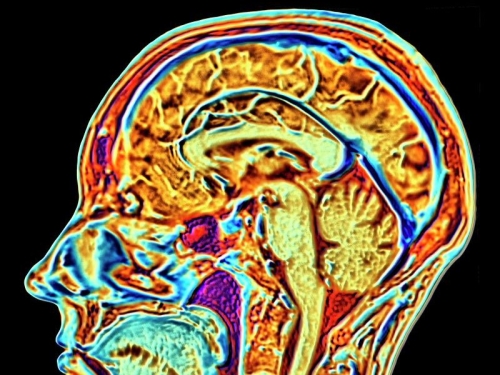

AI spots early mental illness

A new artificial intelligence (AI) is capable of spotting mental health conditions by sifting through brain imaging data to find patterns linked to autism, schizophrenia and Alzheimer’s.